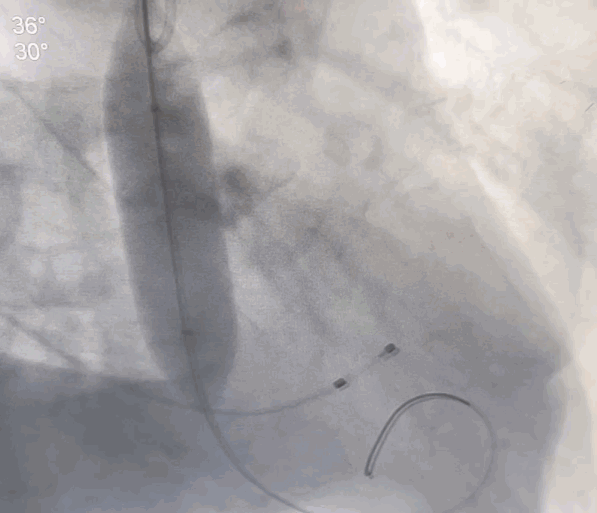

经右侧颈动脉途径,直头导丝跨瓣成功后送入猪尾导管至左室,置入22F动脉鞘管。结合术前CT,装配好VitaFlow Liberty™27号瓣膜,在加硬导丝支撑下,送导管输送系统至主动脉根部并跨过主动脉瓣口,主动脉根部造影,确认瓣膜处于理想位置,在起搏下,经过慢释放、快释放及终释放,完成瓣膜释放过程。术后病人生命体征平稳,跨瓣压差明显改善,无瓣周漏。

瓣膜释放完成

瓣膜形态良好,无瓣周漏